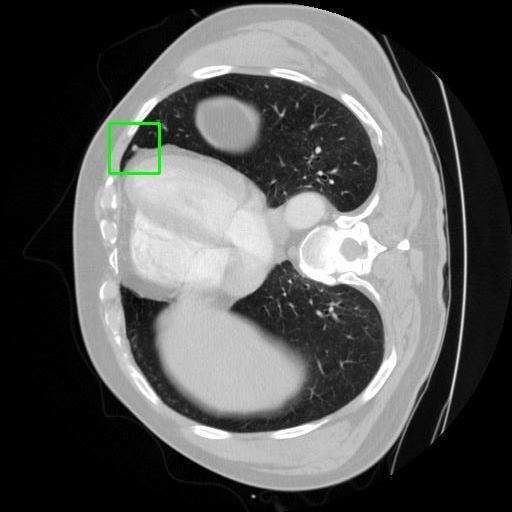

We developed an AI-based system using deep learning models for analyzing lung CT scans to detect and classify pulmonary nodules. We chose the YOLOv11 architecture for its enhanced object detection capability and adapted it specifically for medical imaging, incorporating pixel-level precision and severity classification.

Classification into three severity levels with colored bounding boxes.

Successfully built and deployed an AI model (YOLOv11) capable of detecting lung nodules in CT scans with high accuracy and real-time performance.

Designed a severity classification system that categorizes nodules into null, moderate, and severe using colored bounding boxes, assisting in rapid clinical decision-making.